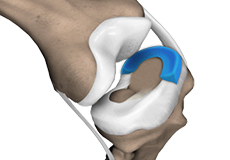

Meniscal Tears

A meniscal tear is a common knee injury in athletes, especially those involved in contact sports. A sudden bend or twist in your knee causes the meniscus to tear.

Meniscal Injuries

Meniscal tears are one of the most common injuries to the knee joint. It can occur at any age but are more common in athletes involved in contact sports. The meniscus has no direct blood supply and for that reason, when there is an injury to the meniscus, healing is difficult.